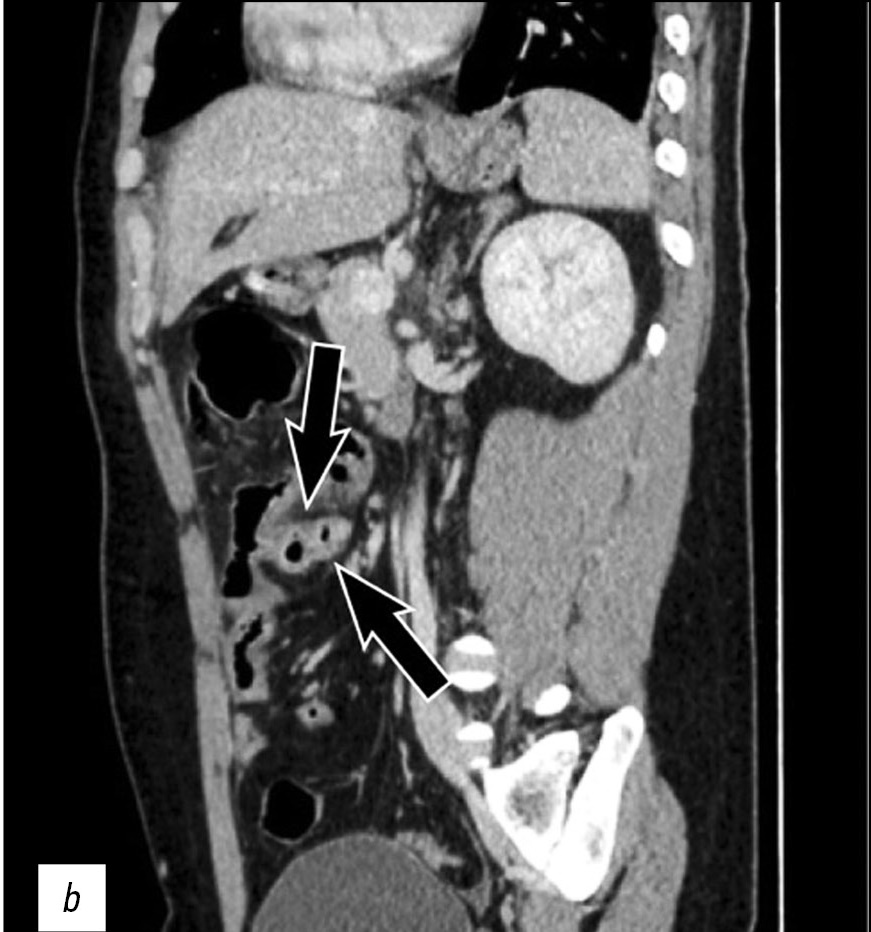

Perforated Meckel’s diverticulum in a young male patient: a case report

Resumo

The case of a 26-year-old male patient with perforation of Meckel’s diverticulum, a rare complication of the most common congenital anomaly of the gastrointestinal tract, is reported in this article. This congenital condition can remain asymptomatic for a long time, and it can get complicated with diverticulitis, enteroliths, neoplasms, and rarely perforation, as in this case.

A preoperative radiological assessment is of fundamental importance for proper diagnostic and therapeutic management of the patient. In this article, we present the typical tomographic imaging features of this infrequent complication to assist radiologists in detecting it.

465-470